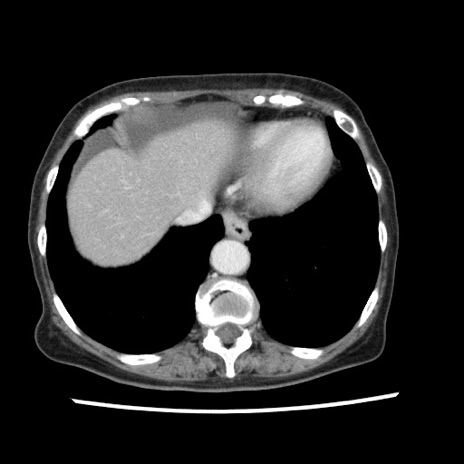

【症例】80歳代女性

【主訴】腹痛

【現病歴】8時間前から腹痛あり来院。

【既往歴】糖尿病、脂質異常症、子宮体癌にて子宮全摘術

【身体所見】意識清明・会話良好だが腹痛で苦悶様、全腹部にわたって反跳痛と圧痛あり

【データ】WBC 13600、CRP 0.14、LDH 224、CK 90